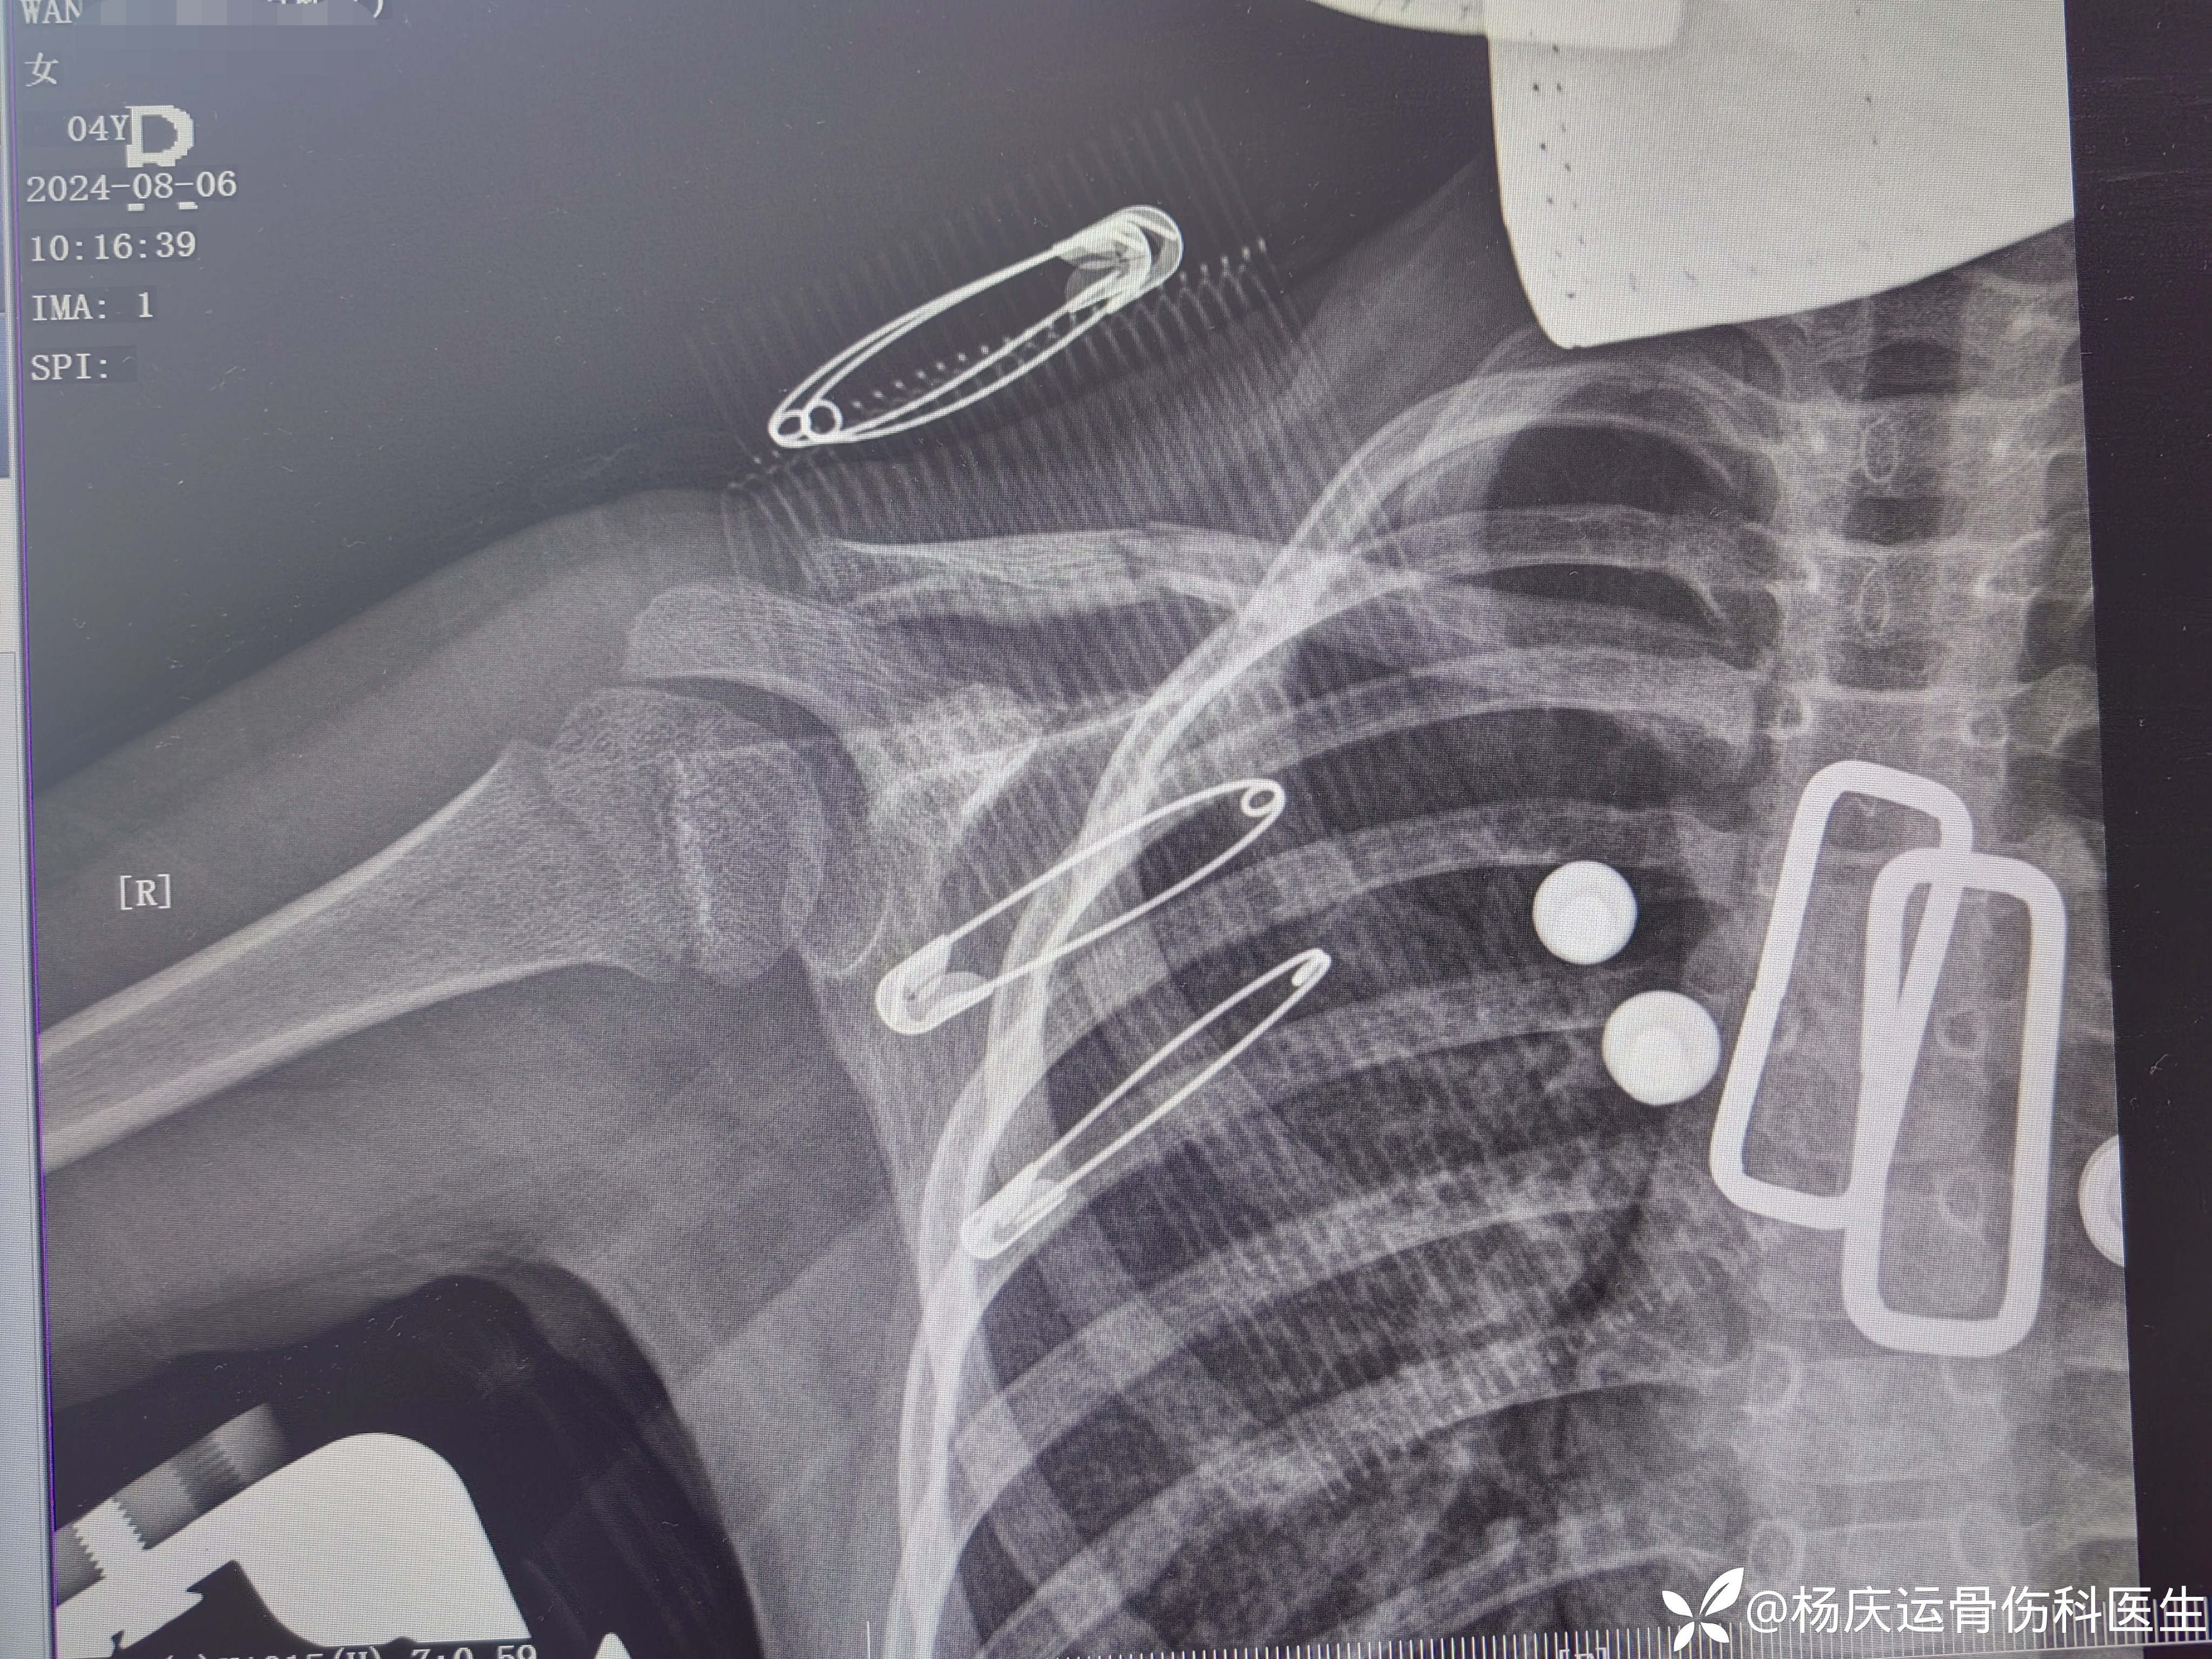

13天复查